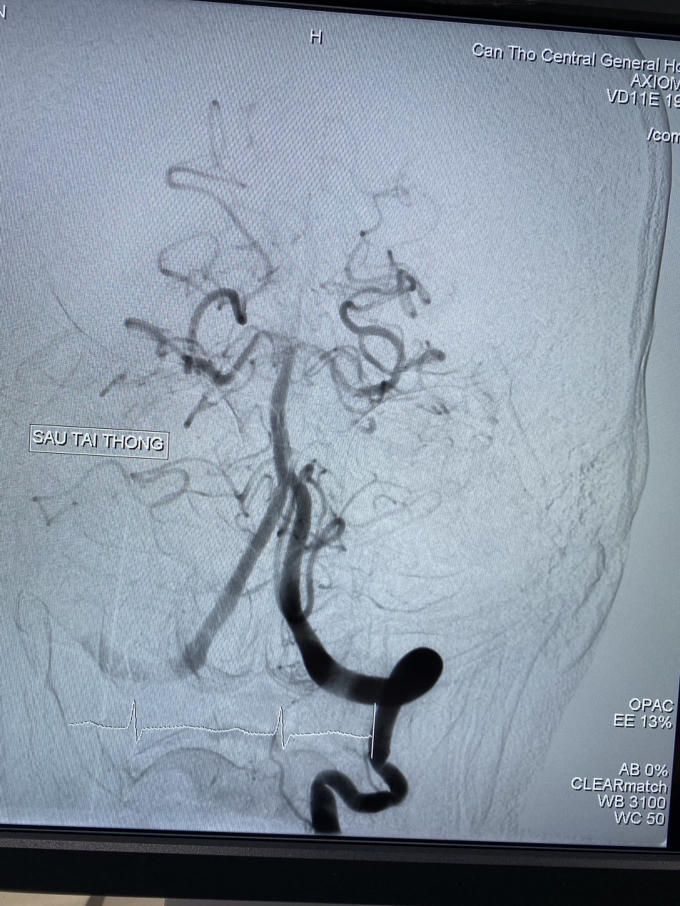

Ê-kíp can thiệp nội mạch do Ts .Bs Hà Tấn Đức Trưởng khoa đột quỵ - Bs CK1 Trần Công Khánh phó khoa chẩn đoán hình ảnh thực hiện can thiệp trong 10 phút đã tái thông hoàn toàn động mạch bị tắc, hút ra được rất nhiều huyết khối.

Hình ảnh động mạch thân nền sau can thiệp tái thông.